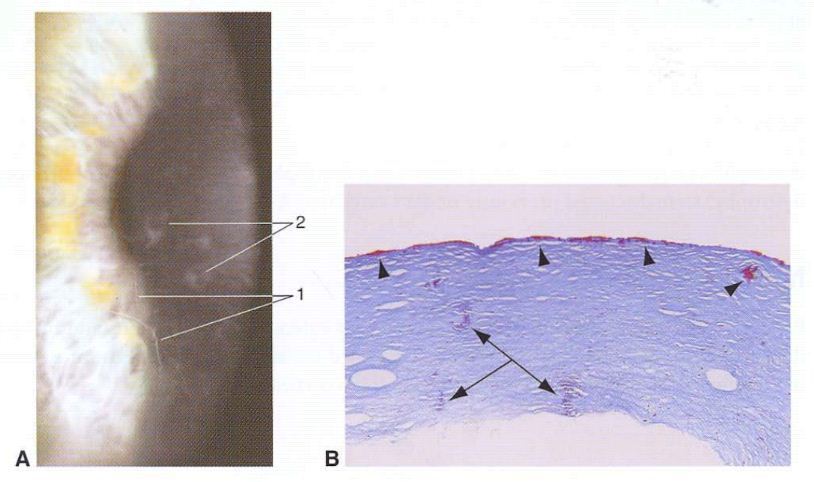

What do the images demonstrate? And what are the highlights?

The normal cornea. Epithelial basement membrane (EBM), Descemet memembrane, endothelium and pre-Descemet membrane layer.